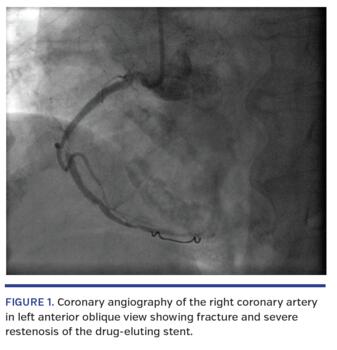

The first in-stent restenosis occurred on day 62 in a 66-year-old man with end-stage kidney disease on hemodialysis. During the index procedure, he was found to have an in-stent restenosis of a drug-eluting stent in a calcified proximal left anterior descending coronary artery implanted 6 months prior. He was treated with 8 cycles of lithotripsy using a 4.0 x 12 mm S-IVL balloon within the previous stent. This was followed by a drug-coated balloon without further stent placement. Given the recurrent restenosis, he required further PCI and stenting. The second restenosis occurred on day 242 in an 84-year-old female. During her index procedure, a diffusely diseased right coronary artery was treated with 8 cycles of lithotripsy using a 3.5 x 12 mm S-IVL balloon, followed by 2 overlapping drug-eluting stents (3.0 x 48 mm and 3.5 x 18 mm Xience Xpedition; Abbott Vascular). On the repeat coronary angiogram, a stent fracture and severe restenosis were identified within the 3.0 x 48 mm drug-eluting stent, at the bifurcation of the right marginal branch (Figure 1). This area of restenosis was treated with a 3.5 x 12 mm Synergy drug-eluting stent (Boston Scientific).